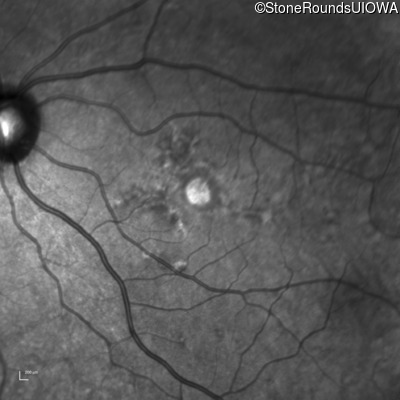

Infrared Fundus Photograph - Right - 20/20 +2

Exemplar

Infrared Fundus Photograph - Left - 20/40 -2